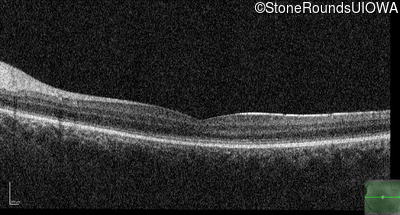

Optical Coherence Tomography - Right - 10/200

Exemplar / OCT Stack

Optical Coherence Tomography - Left - 10/100